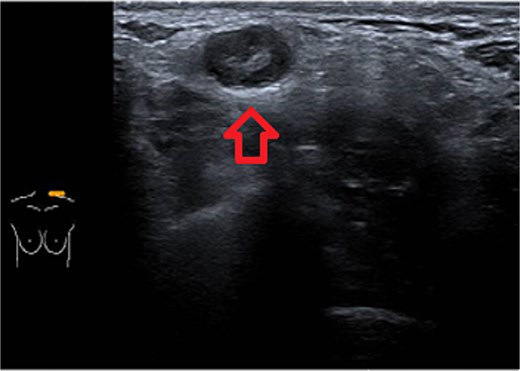

One week later, the patient reported a new lump in the left supraclavicular area. Examination revealed a 2 × 3 cm, nontender, mobile mass, confirmed by ultrasound to be silicone deposition (Figs 3 and 4). Increased breast swelling and lymphadenopathy were attributed to implant rupture and silicone migration.

Typical snowstorm appearance of supraclavicular silicone lymphadenopathy.